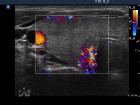

Ultrasonography: Both lobes were enlarged, moderately hypoechogenic, inhomogeneous and displayed increased vascularization.

Diagnosis: Graves' hyperthyroidism.